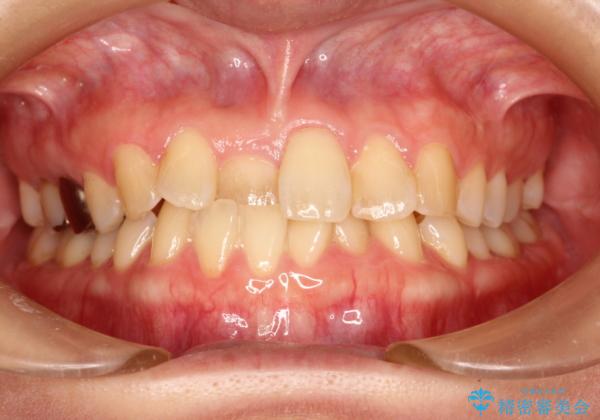

- 前歯の歯並びが気になるとのことで来院されました。

右上の1番目の歯が内側に入り込んでしまっており、その歯がの先端がすり減ってしまっていました。

インビザラインによる矯正治療で前歯の歯並びを改善し、セラミッククラウン装着により歯の形態の回復をする計画としました。

矯正とセラミックを併用することで、より完成度の高い状態に仕上げることができました。